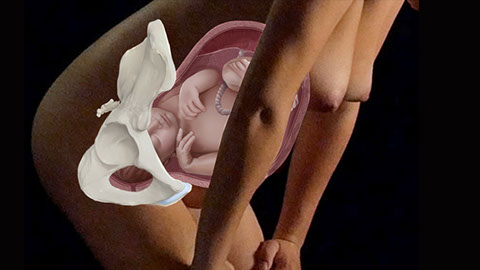

The film „The safe Birth“ follows the physiological birth.

It shows how complex birth is from the moment the child gives the signal to be ready to be born.

The film shows how the neuro-endocrine system works in a physiological birth and how disturbing this process can lead to bad outcomes and physiological birth is a very safe program we have in our reptile brain.

„Currently in Austria and Germany less than 5% of women give birth without any obstetric intervention although considering the given circumstances at least 95% of the women could give birth naturally and without any help or intervention. In only 5% of births is obstetric help actually needed.

What 90% of women are told is medical relief to help the birth,

is not only unnecessary but risky and harmful.

Prof. Dr. Alfred Rockenschaub chair of Ignaz Semmelweis Frauenklinik in Vienna from 1965 to 1985

with a C-section rate of around 1% in during this period

To leave no doubt: we want to point out that emercency medecine, C-Sections and intensive care are a blessning for those who need it.